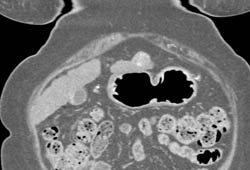

2 Cm Hepatocellular Carcinoma (Hepatoma) Left Lobe of the Liver